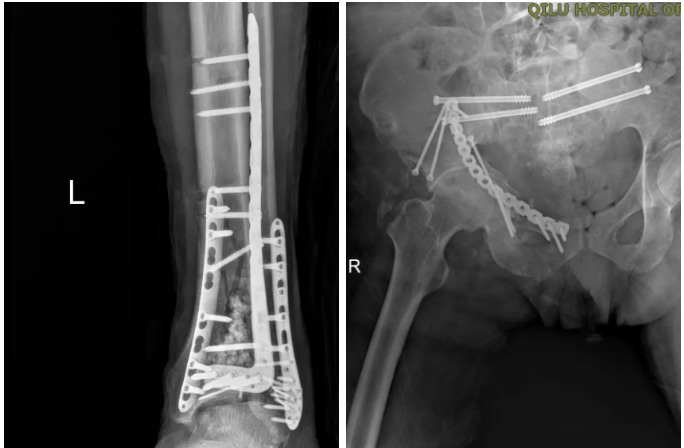

在患者生命体征稳定、感染得到有效控制后,创伤救治工作正式从“保命”转入“功能重建”阶段。团队严格遵循《创伤与重症监护加速康复指南(ERATIC)》,通过精准骨折复位内固定,为患者后续功能康复奠定基础。3月13日,急诊外科团队率先开展高难度骨盆重建手术。因患者骶骨粉碎性骨折移位明显,血压及身体状况无法耐受开放性大手术,且骨性结构破坏严重,置钉难度极大。主刀医生刘涛主任反复调整操作角度、精细操作,成功置入4枚骶髂螺钉,实现稳固固定,顺利完成手术。3月20日,团队为患者实施左胫腓骨远端骨折切开复位内固定术,成功复位骨折、稳固固定,恢复左下肢正常力线;3月24日,再次实施右髋臼陈旧性骨折切开复位内固定术+股神经探查松解术+抗生素人工骨植入术,一举实现骨折修复、神经松解、感染预防三大目标。

骨折终极固定术后复查影像